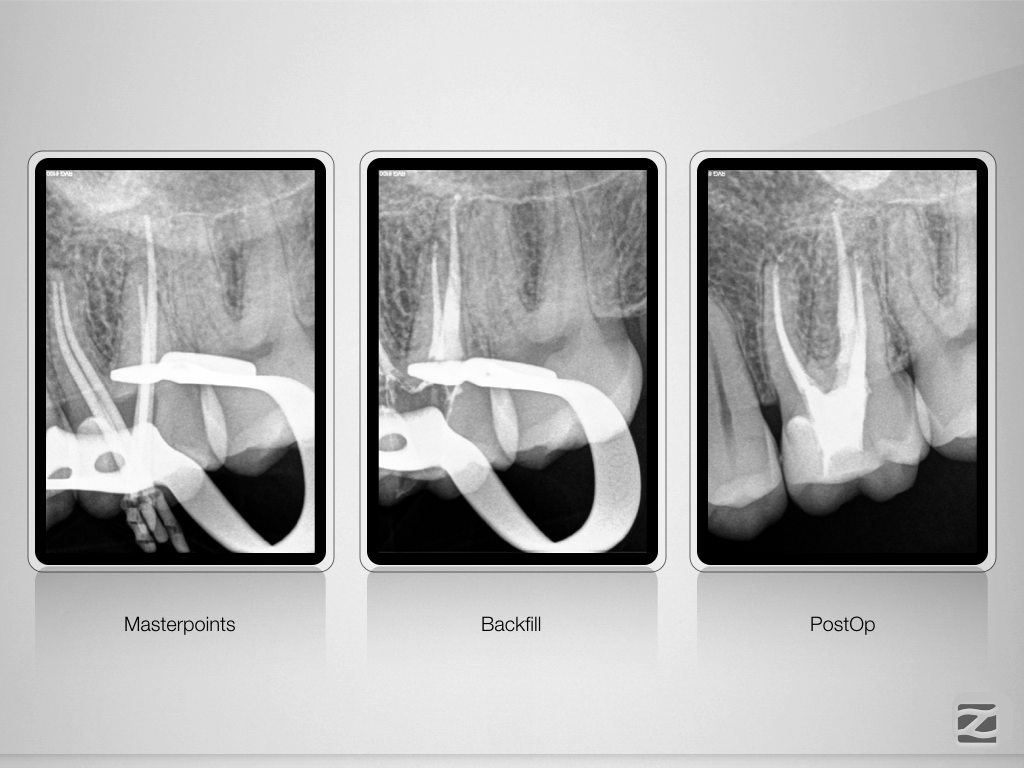

26D.011

Fluch und Segen!